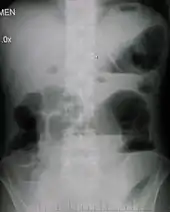

| Upright abdominal X-ray demonstrating a small bowel obstruction. Note multiple air fluid levels. | |

Radiological signs of bowel obstruction include bowel distension and the presence of multiple (more than six) gas-fluid levels on supine and erect abdominal radiographs. Ultrasounds may be as useful as CT scanning to make the diagnosis.[17]